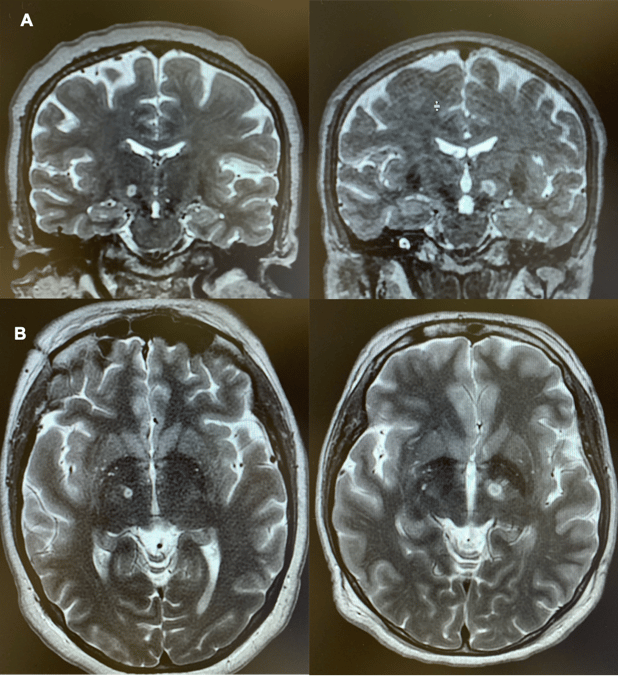

Figure 1. Magnetic Resonance Images in Two Patients Immediately After MRgFUS Subthalamotomy. Coronal (A) and axial (B) T2-weighted views obtained immediately after the procedure. The site of the lesion is recognizable by a heterogeneous central area corresponding to tissue necrosis, which is typically hypointense (black) on T2-weighted images. This zone is delimited by a rim of perilesional cytotoxic edema, hyperintense (white) on T2-weighted images. An additional hyperintense area on T2-weighted imaging corresponds to edema spreading within the white matter surrounding the subthalamic nucleus.